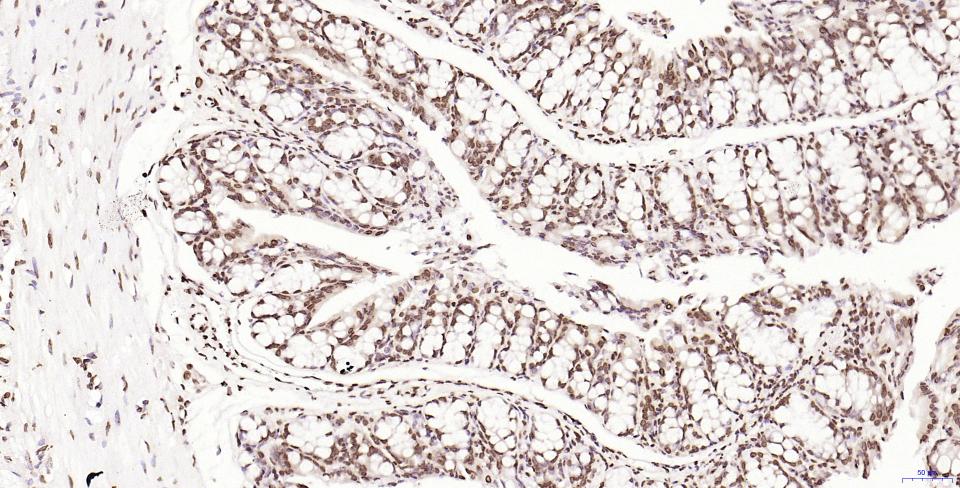

Paraformaldehyde-fixed, paraffin embedded Human Colon Cancer; Antigen retrieval by boiling in sodium citrate buffer (pH6.0) for 15 min; Antibody incubation with Histone H2A.X Monoclonal Antibody, Unconjugated(bsm-61080R) at 1:200 overnight at 4°C, followed by conjugation to the SP Kit(Rabbit, SP-0023) and DAB (C-0010) staining.

Paraformaldehyde-fixed, paraffin embedded Human Colon; Antigen retrieval by boiling in sodium citrate buffer (pH6.0) for 15 min; Antibody incubation with Histone H2A.X Monoclonal Antibody, Unconjugated(bsm-61080R) at 1:200 overnight at 4°C, followed by conjugation to the SP Kit(Rabbit, SP-0023) and DAB (C-0010) staining.

Paraformaldehyde-fixed, paraffin embedded Mouse Colon; Antigen retrieval by boiling in sodium citrate buffer (pH6.0) for 15 min; Antibody incubation with Histone H2A.X Monoclonal Antibody, Unconjugated(bsm-61080R) at 1:200 overnight at 4°C, followed by conjugation to the SP Kit(Rabbit, SP-0023) and DAB (C-0010) staining.

Paraformaldehyde-fixed, paraffin embedded Rat Colon; Antigen retrieval by boiling in sodium citrate buffer (pH6.0) for 15 min; Antibody incubation with Histone H2A.X Monoclonal Antibody, Unconjugated(bsm-61080R) at 1:200 overnight at 4°C, followed by conjugation to the SP Kit(Rabbit, SP-0023) and DAB (C-0010) staining.